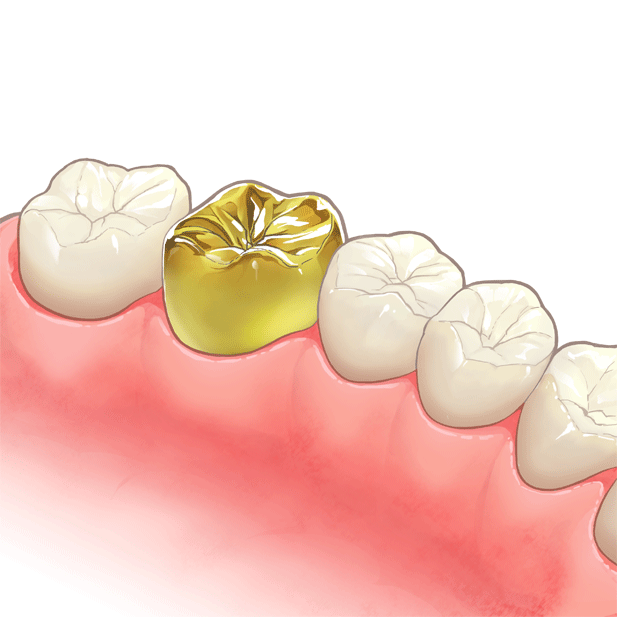

⑥ 前回詰めた綿花の状態を確認して、良い状態なら、「根管充填剤」(マスターポイント・アクセサリーポイント)というお薬を、余分な空間がないように根っこに詰めます。

⑥ 前回詰めた綿花の状態を確認して、良い状態なら、「根管充填剤」(マスターポイント・アクセサリーポイント)というお薬を、余分な空間がないように根っこに詰めます。 Q1.痛みはありますか?

Q1.痛みはありますか? ② 次に、「根管長測定器」という機械を使い、根っこの長さを正確に測ります。

② 次に、「根管長測定器」という機械を使い、根っこの長さを正確に測ります。

⑤ 次に、仮詰めをします。

⑤ 次に、仮詰めをします。 虫歯が神経まで達して炎症を起こしているので、人によってはズキズキとした痛みを感じる方もいます(>_<)

虫歯が神経まで達して炎症を起こしているので、人によってはズキズキとした痛みを感じる方もいます(>_<)